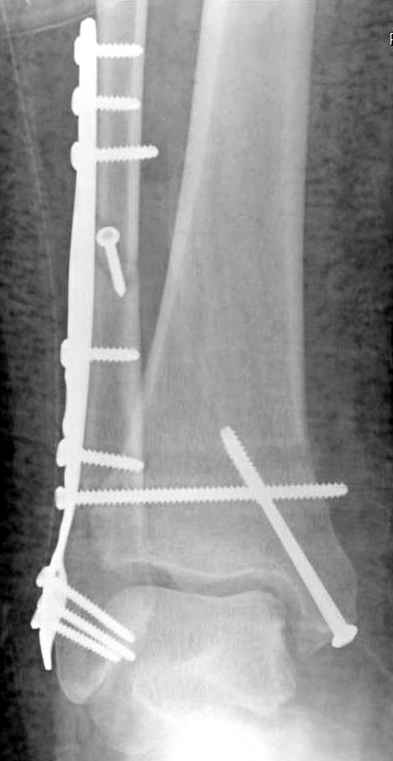

Если до сих ничего не сделано, с артродезом сустава в данный момент я бы повременил, на выставленных январских снимках хорошо сохранившийся сустав, а в "мортиз" (трехчетвертной) и на боковых снимках не менее 5 мм укорочение малоберцовой кости. Косые переломы лучше фиксировать пластинами, как то мы разбирали случай, где было отмечено, что это закон "таранная кость всегда следует за малоберцовой".

В данном случаи я бы уговорил больного на реконструкцию, для этого после удаления шурупов, спереди очистить от рубцов синдесмоз, несросшуюся наружную лодыжку - остеотомия по линии перелома и компрессирующий (lagging technique) кортикальный шуруп 3.5 мм по поперечнику остеотомии. Следующий этап - восстановление длины малоберцовой за счет удлинения, сделать поперечную остеотомию где-то на уровне сантиметр выше вашего синдесмозного шурупа, наложить длинную пластинку, прикрепить пластину за дистальный конец двумя или тремя шурупами; сохраняя контакт пластины с костью, имеющимся

compression&tension device AO system (при отсутствии любой lamina spreader подойдет, создать дистанцию между пластиной и шурупом, проведенным проксимальнее пластины) толкая проксимальный отдел пластины, низвести пластину, мортиз рентгенограмма подскажет на сколько. Если заранее сделать предоперационный план (ренгенограмма другой стороны), тогда точно можно определить, на сколько вам необходимо сделать поперечную остеотомию малоберцовой кости, для закрытия создавшегося дефекта.

Убедившись, что желаемая длина восстановлена, окончательная фиксация пластины, при этом через пластину пару 3.5 мм шурупов на синдесмоз, предпочтительно в четыре кортекса и оставить на 3 мм длиннее, если под нагрузкой синдесмотический шуруп сломается, сломанный конец легче удалить с медиальной стороны.

Медиальная сторона не в нагрузочной зоне, и там большая дыра - если есть 2.7 мм шурупы, или пару спиц в ваших условиях или методика Лазарева. Необходимо уделить внимание к мягким тканям, обнажается кость с латеральной стороны и у места где проводится остеотомия.

После 5-6 недели после травмы сделана повторная операция, обошлись без удлинения малоберцовой.